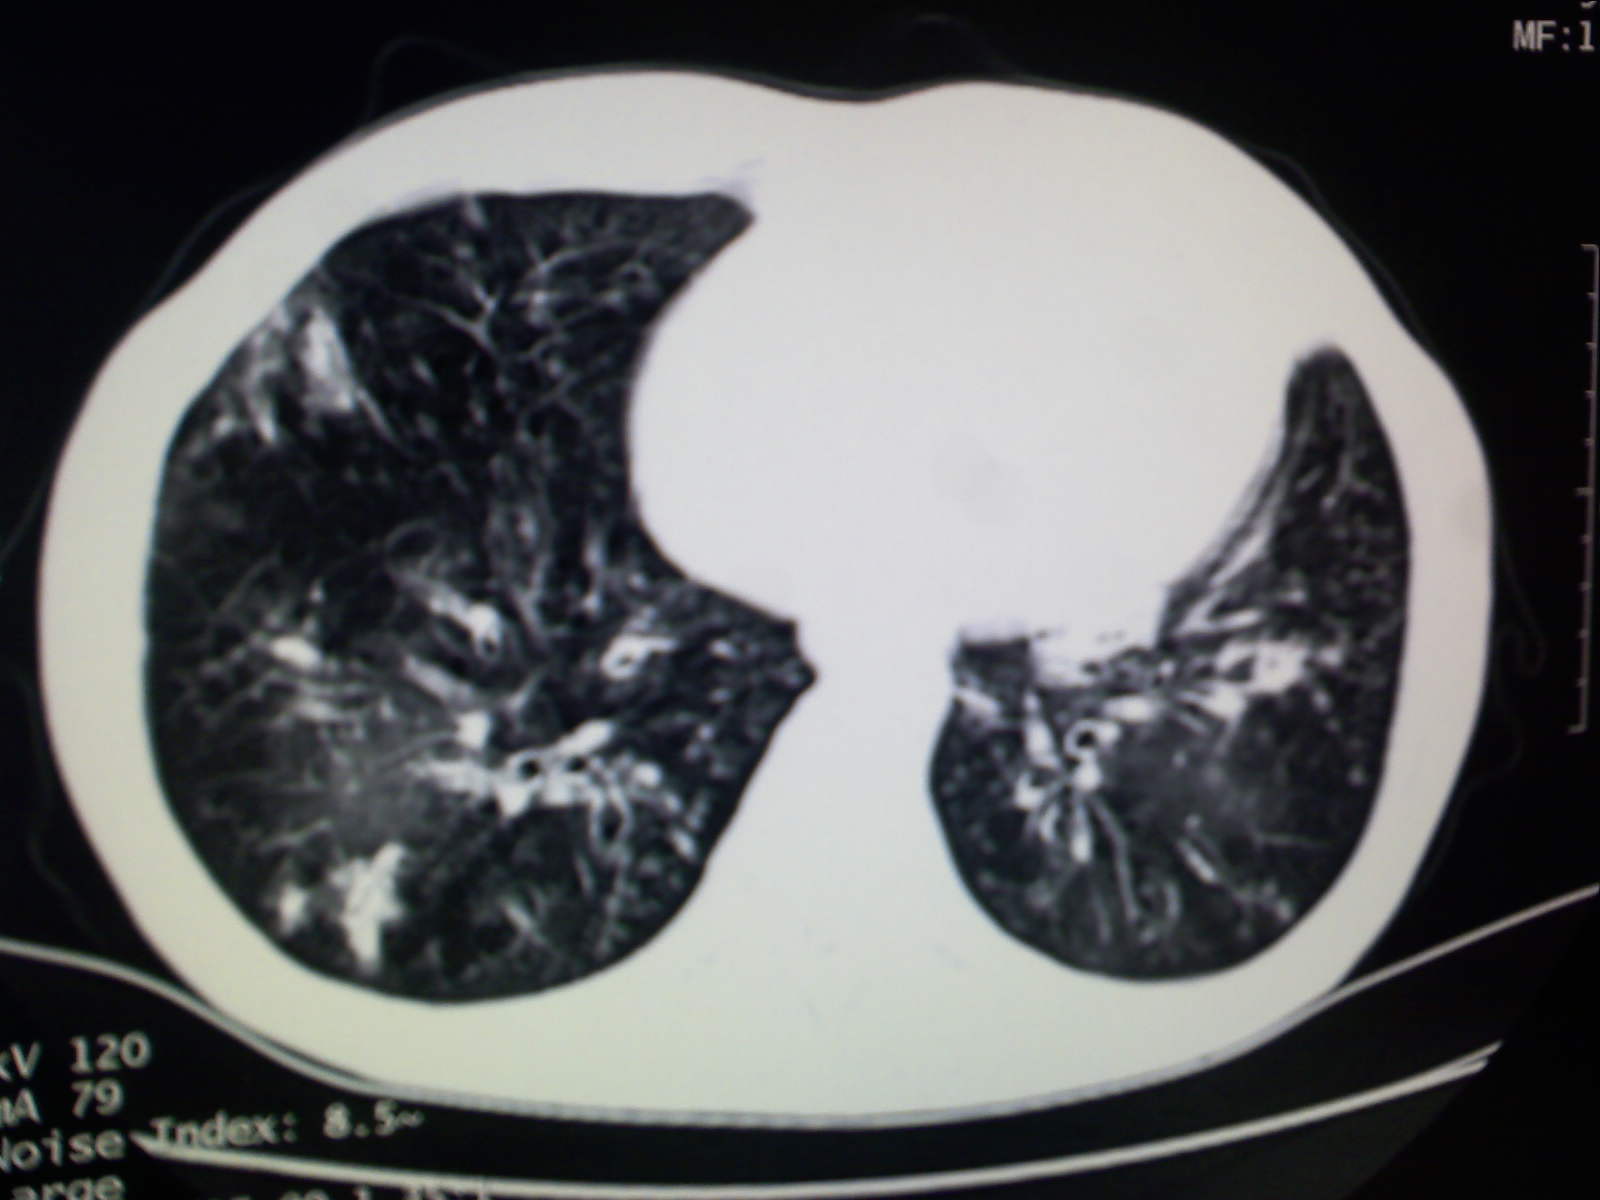

以下是引用卜一在2009-4-11 15:50:00的发言:[br]双肺继发性肺结核伴空洞形成,不排除合并霉菌感染!(病灶呈多形态 多特征 散在分布)。另:合并支气管扩张征伴感染!

以下是引用主力军在2009-4-11 15:55:00的发言:[br]两肺继发性肺结核可能性大。

以下是引用康鹏在2009-4-11 16:30:00的发言:[br]双肺继发性肺结核伴空洞形成合并感染[br]支气管扩张合并感染